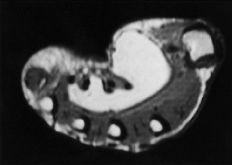

En los casos en los que la tumoración tenía un comportamiento expansivo o estaba próxima a una articulación IF se practicaron estudios radiológicos simples o de alta definición. Se constató, además de un aumento de partes blandas, una erosión ósea cortical con un ribete escleroso, especialmente en los tumores de mayor tamaño o en zonas de reducida capacidad de expansión. Las imágenes de RM mostraron patrones de intensidad variable dependiendo de la nodulación del tumor y de sus depósitos de hemosiderina (Fig. 1).

En cuanto a su sintomatología, los TCG comienzan a doler en relación con su aumento de volumen. Se comportan con agresividad local, invadiendo los compartimentos vecinos e incluso erosionando el hueso subyacente.2,5,6,9,13,15,17,29,33,37Cuando no son nodulares o claramente superficiales, es de utilidad la radiología convencional y de alta definición, en donde se aprecia un aumento de volumen y densidad de las partes blandas en la mitad de los casos y una erosión ósea con ribete escleroso en el 20% de los casos.2-5,6,9,13,15,17,37 En los estudios de RM es característica una imagen de tumoración nodular debido a los depósitos de hemosiderina, adyacente al tendón o cápsula, con áreas de disminución de intensidad de señal en T1 y T2 y otras zonas de señal isointensa al músculo en T1 e inferior a la grasa, pero superior al músculo en T2 (Fig. 1).17,29

Figura 1. Tumor de células gigantes que afectaba de forma difusa al dedo anular. Corte coronal de RM potenciada en T1 en la que se aprecian cuatro nódulos tumoreales volares que infiltran el canal digital.